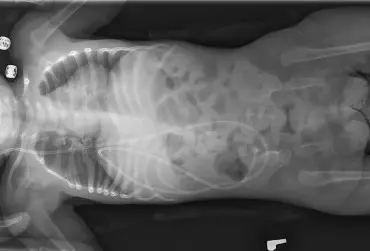

Fizjoterapia w rdzeniowym zaniku mięśni

Rdzeniowy zanik mięśni jest chorobą genetyczną, w przypadku której istotną rolę  odgrywa rehabilitacja dostosowana do aktualnego stanu funkcjonalnego pacjenta,  a cały program leczenia wymaga zastosowania multidyscyplinarnego podejścia.